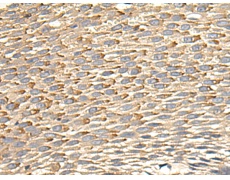

IHC positive control: |

Human lung cancer and Human liver cancer; Human colorectal cancer and Human esophagus cancer |

IHC Recommend dilution: |

100-500 |